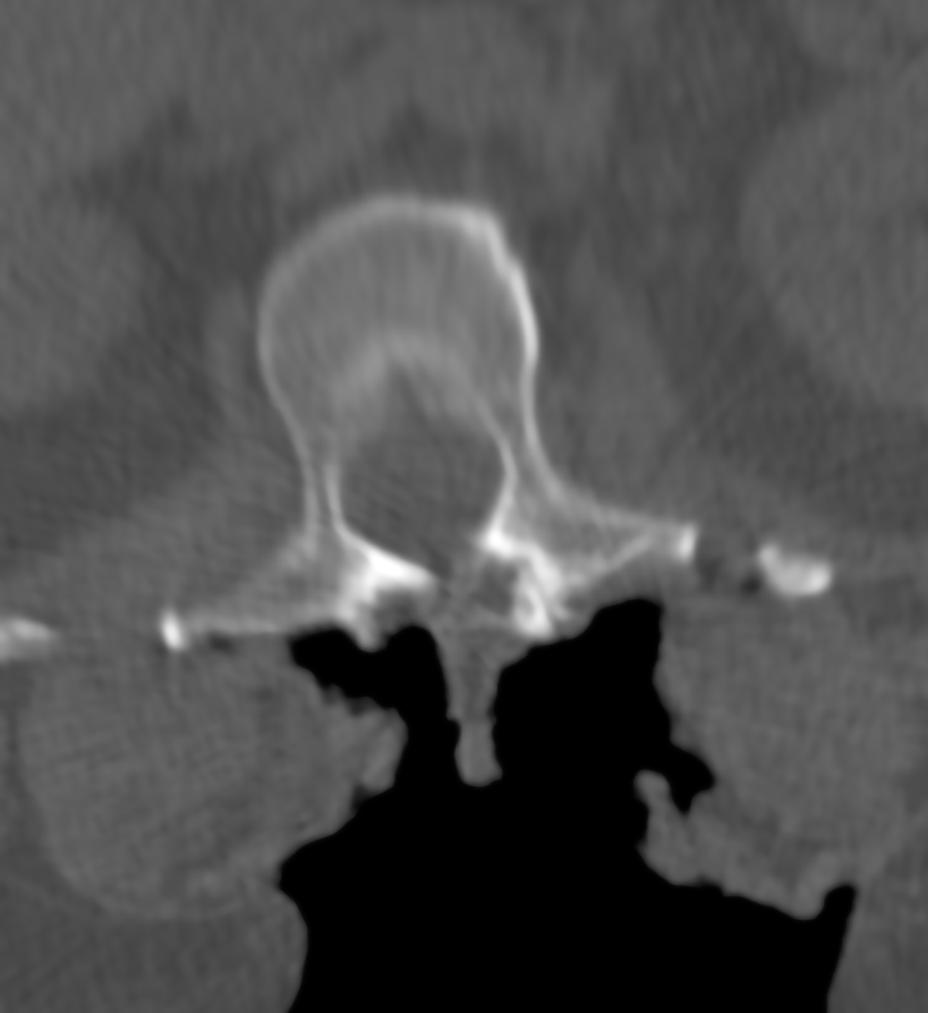

Avvikende anatomi støter vi på ved anomalier samt ved primære og sekundære deformiteter som skoliose og bruddsekvele, hvor ryggvirvlene og pediklene er roterte eller har en unormal helningsgrad. Dessuten har noen pasienter svært grasile pedikler (Bilde 2). Anatomiske landemerker kan også være dekket av beinbroer etter tidligere kirurgisk avstivning av ryggen, eller maskert av ankylose. Ved ryggfiksasjoner høytorakalt er ofte ryggsøylen dårlig framstilt på gjennomlysning – det skyldes strukturer som projiseres over ryggsøylen (skuldre, brystkasse, organer i brysthulen). Endelig er det en iboende begrensing i å anvende todimensjonal (2D) gjennomlysning for å visualisere og instrumentere en tredimensjonal (3D) struktur. Det krever lang erfaring å lære å «oversette» 2D til 3D bilder.

BILDE 2: Pasient med grasile pedikler før (A) og etter instrumentering (B)